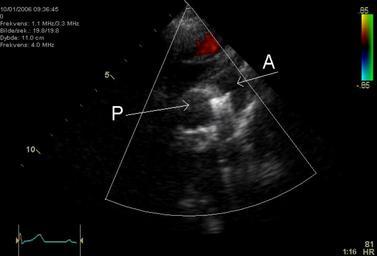

MAKE A MEME View Large Image PDA Coil.png An echocardiogram of a coiled persisting ductus arteriosus One can see the aortic arch the pulmonary artery and the coil between them Image made by myself Kjetil Lenes Released in agreement with my employer Keywords en ...

Keywords: PDA Coil.png An echocardiogram of a coiled persisting ductus arteriosus One can see the aortic arch the pulmonary artery and the coil between them Image made by myself Kjetil Lenes Released in agreement with my employer Keywords en Echocardiography Sonography Ultrasonography Medical Ultrasound Cardiology persisting ductus arteriosus de Echokardiographie Sonografie Sonographie Ultraschall Kardiologie ductus arteriosus Echocardiography Patent ductus arteriosus